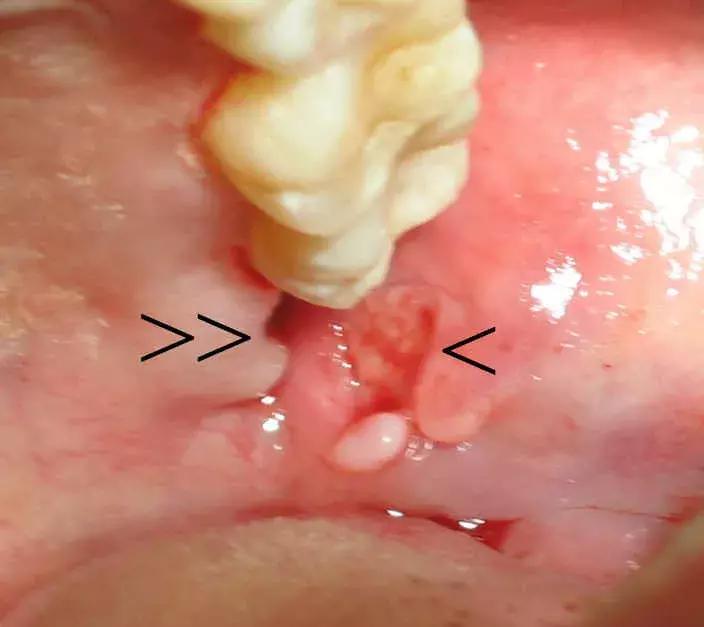

2、阻生齿拔除20天后,

牙床肿了一个包是咋回事?

图片看不太清,根据病史和上牙列情况,可能是粘液囊肿。上颌牙齿反复咬破下牙床引起的。